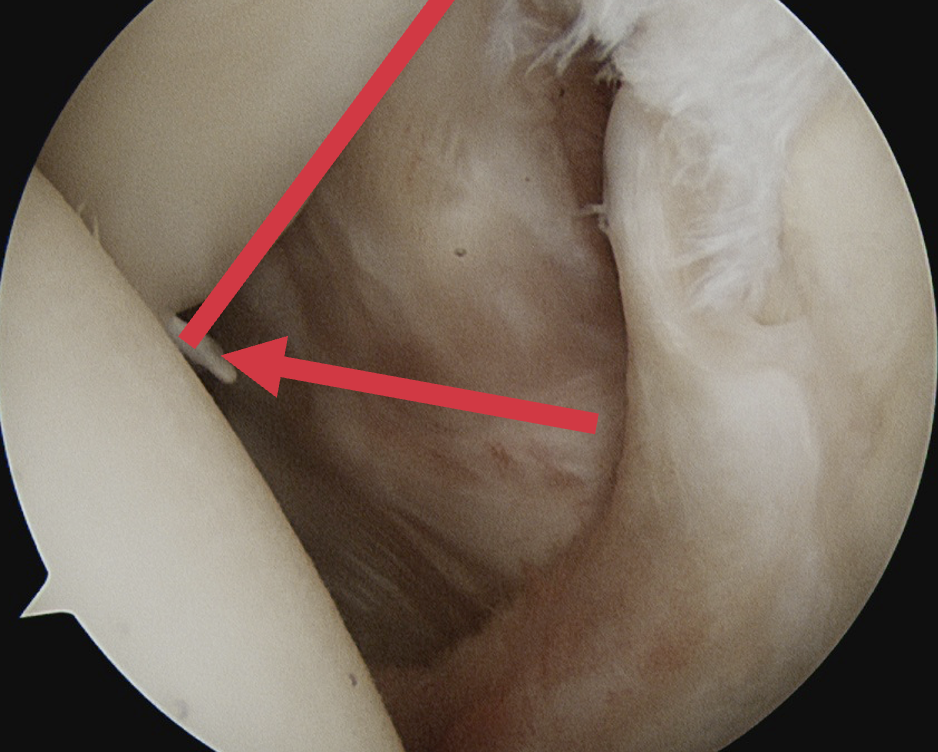

Comma sign

- medially retracted subscapularis tear

- exposes the superior insertion of superior glenohumeral ligament / coracohumeral ligament

Full thickness retracted subscapularis tear with comma sign